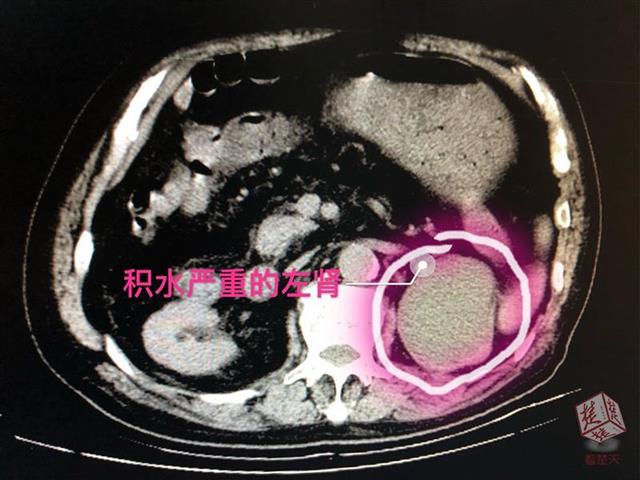

经检查,泌尿外科专家李辉明主任发现,患者左侧输尿管上段被一颗直径约1.2厘米的结石堵住,已出现重度肾积水并感染(肾积脓)。“明明一直在吃排石药,怎么石头还在呢?”老人觉得奇怪。排石药一般都具有利尿、扩张输尿管的作用,服用后原本稳定的肾内结石会随尿液下排,很易在输尿管狭窄处产生滞留,李辉明解释,正是由于赵爹爹的结石卡在了输尿管上段,随着尿液中结晶成分不断附着,结石越变越大,便形成了梗阻。时间长了,尿液排不出去,把肾脏憋成了一个只进不出的“水囊”,目前,积水已达200ml,老人出现的腰痛、高烧、血尿等病症便是结石梗阻产生的急性症状。

当务之急,为解除梗阻,引流肾脏积液避免病情加重引发重度感染危及生命,李辉明建议老人住院,接受左侧经皮肾穿刺造瘘引流,待感染控制后才能进一步碎石取石,进行彻底治疗。